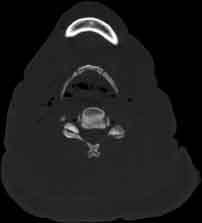

Visible Human male: Sectio transversalis 1228

CT

NMR

Pd T1 T2